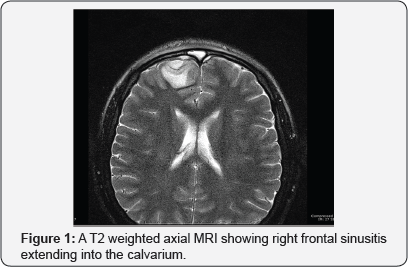

Imaging studies were conducted and showed what appeared to be an epidural collection in the frontal area, right frontal sinusitis, and ethmoid sinusitis with preseptal cellulitis and extension into epidural space in the frontal region. MRI showed paranasal sinus opacification with intracranial extension, extraaxial empyema formation, dural and leptomeningeal enhancement with some focal meningitis. These findings were consistent with Pott's puffy tumor, a rare syndrome associated with frontal sinusitis (Figure 1-3).